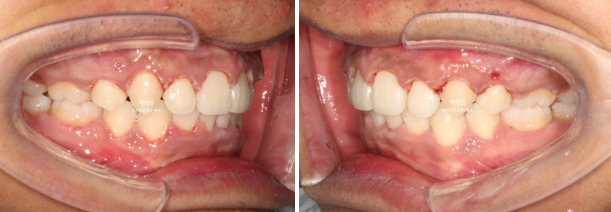

2년 전 교정치료를 이어받기 위해 오신 외국인 환자분입니다.

외국에서 발치교정 진행 중 브라켓을 붙인 채로 치료 도중 오셨으며 한국에 머무르게 되어 치료 마무리를 위해 오셨습니다.

사진은 브라켓을 뗀 후 사진이고, 위 앞니가 아랫니를 많이 덮는 과개교합이 보입니다.

아랫니가 안 보일 정도의 심한 과개교합 입니다.

위 아래 발치공간이 절반 이상 남아있는 상황입니다.